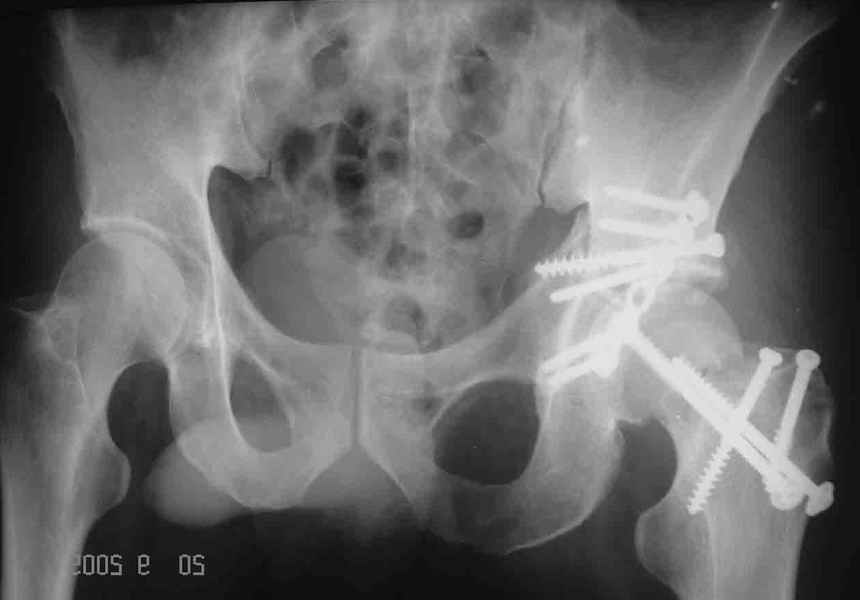

Уважаемые коллеги. Больной был оперирован в одну сессию 25 августа. Сначала на голень наложен спице-стержнвой аппарат. Затем выполнен остеосинтез вертлужной впадины Y-образным доступом. Пришлось дополнительно отсекать вертел. Шейка синтезирована спонгиозными винтами и спицами, вертел - спицами и стягивающей петлей. После операции находился на вытяжении 3 нед. Раны зажили первичным натяжением. Сейчас уже дома. Будет и дальше без нагрузки на левую ногу. Будем наблюдать в динамике. Ждем комментарии.

Обычно мы поступаем так же, однако в этом случае имелся дефект верхней части шейкии, перелом и остеотомия вертельной области, так же с дефектами, спицы - вынужденная мера. Здесь ведь пучок спиц не вместо трех винтов, а в дополнние к двум. Эти-то два пришлось провести чуть ли не с уровня диафиза, проксимальнее было сплошное крошево.

Перелом шейки был многооскольчатйй очень медиальный, по сути шейку и вертел расколотило об подвздошную кость с кучей мелких фрагментов, вертел был полностьб вовлечен в перелом, головка заподлицо скрывалась в расширенной вертлужной впадине. Качество кости приличное. Остатки дуги Адамса с предварительно проведенными винтами я вколотил в головку и компрессировал винтами - оказалось прочно, но образовался дефект верхнего отдела шейки, который был заплнен фрагментами фиксироваными трансфрактурными спицами - отсюда пучек.

Вертел во время доступа пришлось еще рубить, т.к.

переломы распространялись чересчур дистально.

Отсюда еще пучек спиц.